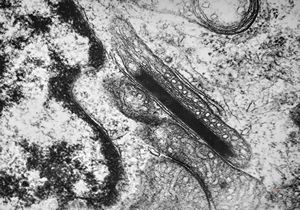

rabbit spinal cord trauma

rabbit spinal cord trauma